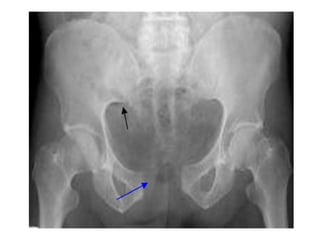

• Pelvic fractures is the major cause of mortality and

morbidity in pts with blunt abdominal trauma.

• MVA and pedestrian account for the majority of

these injuries with mortality b/w 10 and 25%

• Massive haemorrhage and Coagulopathy accounts

for 40-60% of mortality in this group of patients.

Classification of pelvic fractures by Trunkey

• Type I injuries represent crush fracture of the pelvis

and involve three or more elements of the pelvic

ring.

• Type II injuries are unstable injuries and involve at

least two breaks in the pelvic ring

• Type III are stable fractures involving single element

in the pelvic ring, or fracture of pubic rami.

Classification